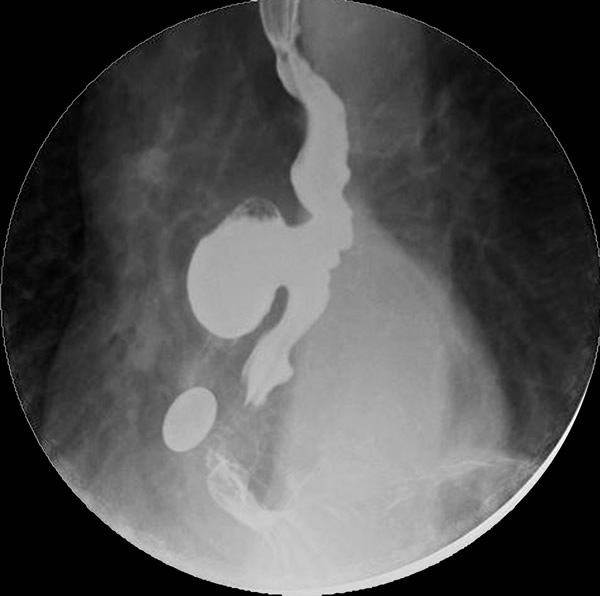

The clinical manifestations are unpredictable and are not influenced by the size of the diverticulum but rather correlate with the underlying motility disturbance. Dysphagia and regurgitation are the predominant symptoms observed. Respiratory complaints, when present, indicate aspiration. Most esophageal diverticuli are found incidentally. Chest radiography may be normal or may reveal a mediastinal density or air-fluid level (Figure 1). This feature may be misdiagnosed as a hiatus hernia. The diagnosis of an epiphrenic diverticulum is usually made on an upper gastrointestinal series (Figure 2). Oblique views can define the size, location, number and shape of diverticula. Contrast studies, however, are unreliable for evaluating motility patterns and thus esophageal manometry should be performed preoperatively. Correct placement of the catheter can be difficult and may be assisted with endoscopic guidance. Esophageal endoscopy is recommended to exclude other etiologies for dysphagia. This maneuver can be difficult and should be performed by an experienced endoscopist.